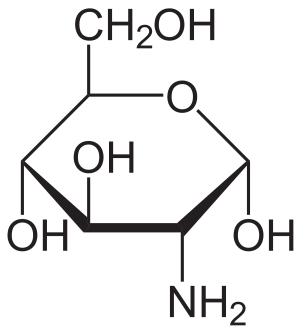

Wat is glucosamine?

Glucosamine is een natuurlijk voorkomende stof die in het menselijk lichaam onder andere wordt aangemaakt in gezonde kraakbeencellen. Glucosamine trekt vocht aan zodat schokken beter geabsorbeerd kunnen worden. Het zorgt er zo voor dat het kraakbeen zijn stevige, doch soepele eigenschappen behoudt en het is een belangrijk bestanddeel van gewrichtsvloeistof.

Op latere leeftijd gaat het kraakbeen minder glucosamine aanmaken. Hierdoor wordt er minder vocht vastgehouden en kunnen schokken minder goed worden geabsorbeerd. Dit is waarschijnlijk mede bijdragend aan de slijtage van gewrichten wanneer iemand ouder wordt. In de voeding komt glucosamine nauwelijks voor. Daarom kiezen mensen er regelmatig voor om glucosamine als supplement te slikken, meestal in een dosering van 1200 tot 1500 milligram per dag. Dit gebeurt vaak in combinatie met twee andere stofjes waarvan wordt geclaimd dat ze de gezondheid van gewrichten bevorderen: chondroitine en MSM (methylsulfonylmethaan).

Afbeelding 3. Glucosamine molecuul